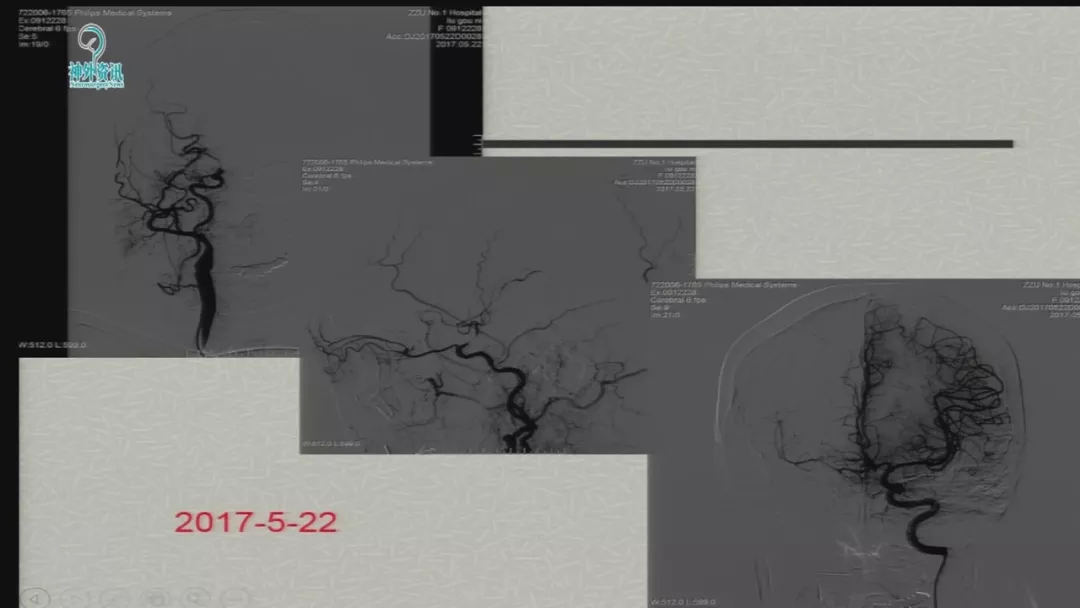

今天为大家分享的是由郑大一附院徐浩文教授在第七届全国介入医学工程大会上带来的“Neuroform EZ在ICAD治疗中的应用”精彩讲课视频和PPT,欢迎观看!(内容未经讲者审核,不当之处请与我们联系)